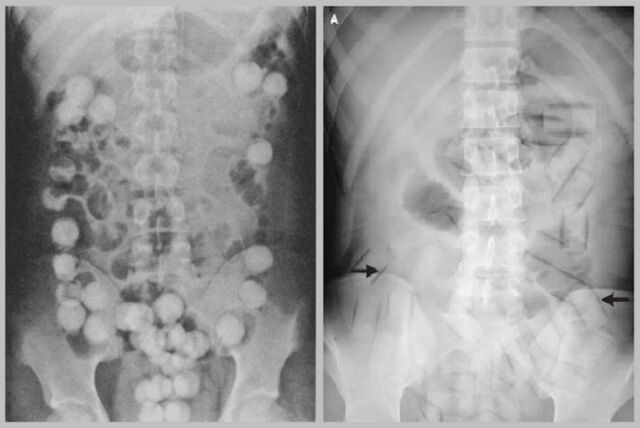

海外からコカインなどの麻薬類を密輸する際、コンドームに詰めて直腸や

膣内に入れて運び込む、運び屋という仕事がありますが数年に一回程度の

割合で飛行機の機内や空港の税関で、体内のコンドームが破れて突然死と

いう例がありますが、あれも吸収の速い直腸や膣内に入れていることから